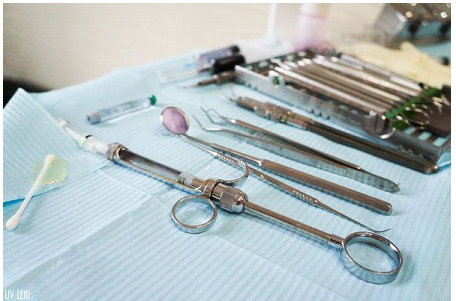

打上麻藥後,開始進行 右邊口腔的牙周刮除術,

雖然看器械好像很可怕,

但因為麻藥的關係,過程中是沒有感覺的,而且相當快速。

由牙助幫我進行 牙菌斑檢測,

這是清除牙菌斑顯示劑的工具。

每次做完牙菌斑顯影,

診所都會貼心的再幫我們清除乾淨唷(不需要自己動手刷的要命XD)